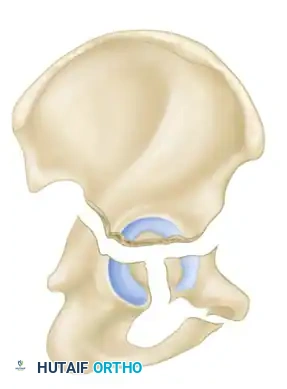

The Letournel and Judet classification system remains the universally accepted framework for categorizing acetabular fractures. It is predicated on the concept of the acetabulum being supported by an inverted "Y" consisting of an anterior column and a posterior column. The system divides fractures into two broad categories: Simple Fracture Types and Associated Fracture Types.

- Transverse Fractures: A single fracture line crosses both the anterior and posterior columns horizontally, dividing the innominate bone into a superior (iliac) segment and an inferior (ischiopubic) segment.

- T-Shaped Fractures: A transverse fracture with an additional vertical fracture line that splits the inferior ischiopubic segment, exiting through the obturator ring.